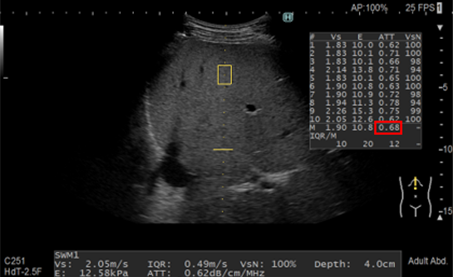

Kỹ thuật không xâm lấn trong đánh giá xơ gan và gan nhiễm mỡ - BS ...